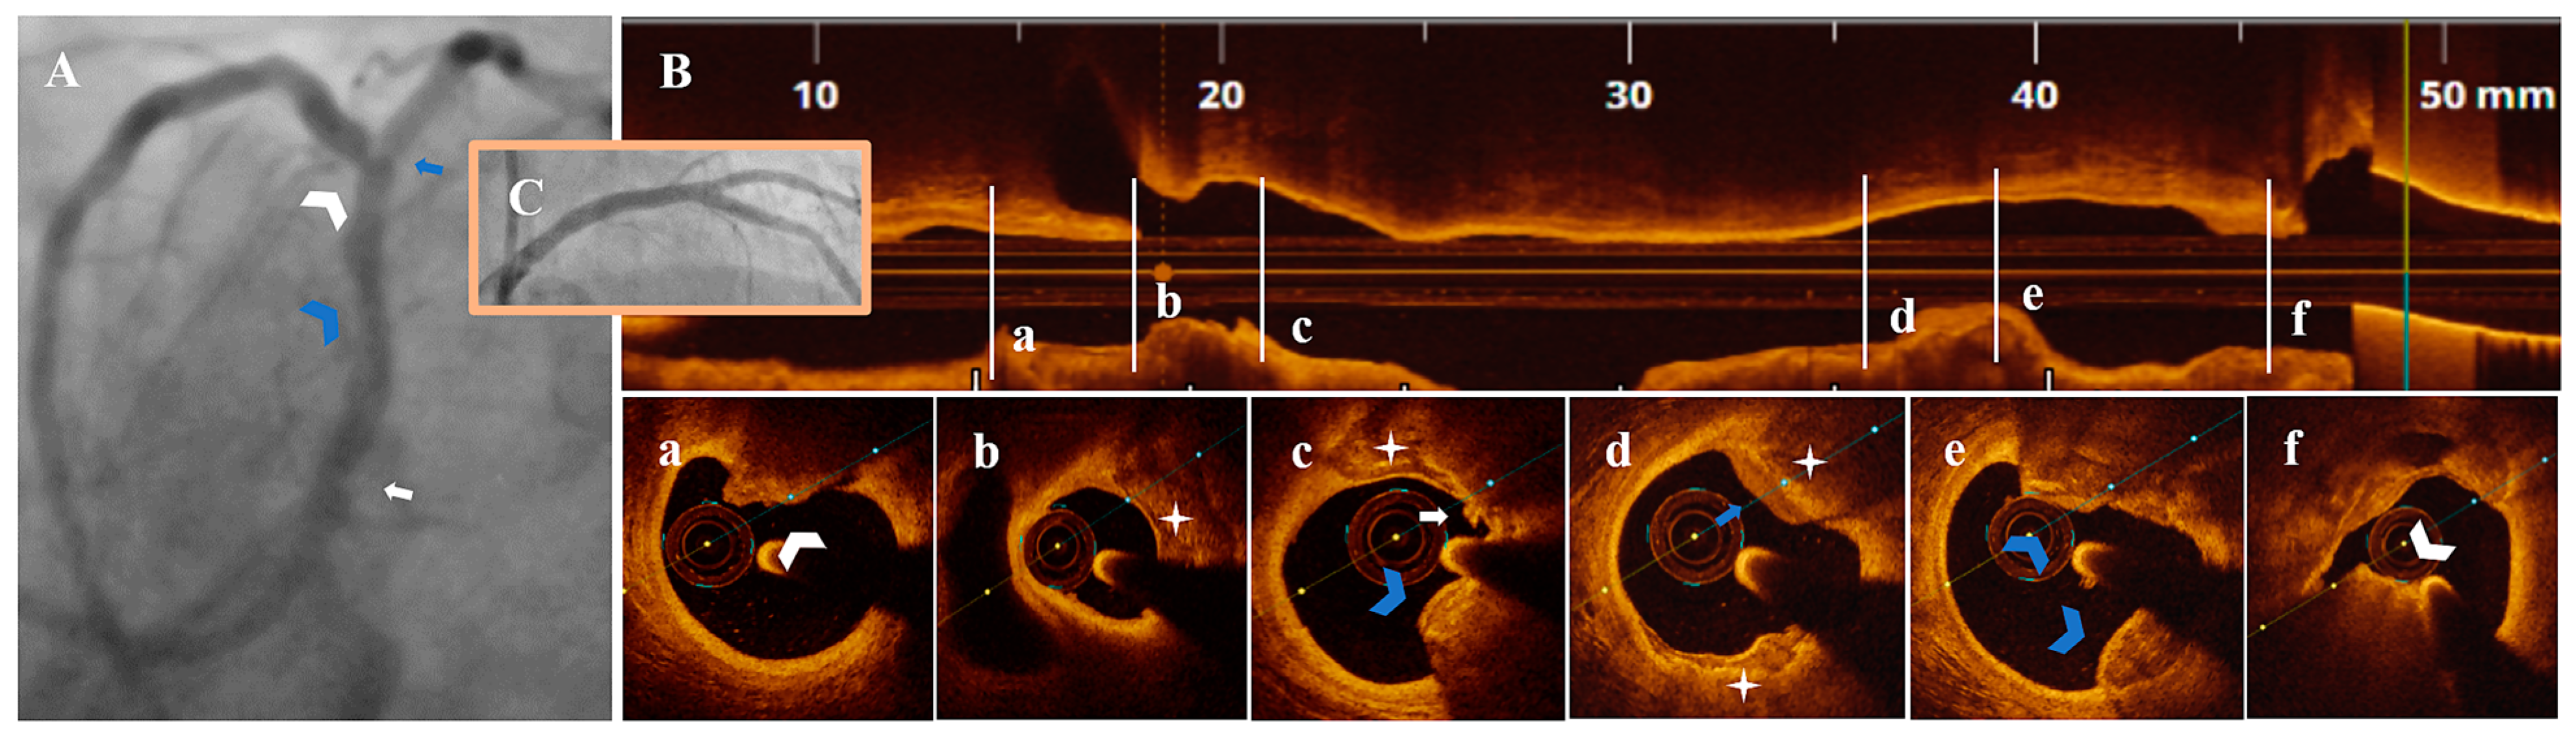

Figure 4.

A 79-year-old patient presenting with NSTEMI. (A) CA—LM with significant proximal stenosis (white arrow), LAD with nonsignificant proximal (blue arrowhead) and severe mid-stenosis (white arrowhead), diagonal branch with borderline ostial stenosis (blue arrow). (B) OCT—LM-LAD plaque longitudinal view. (a–c) Severe mid-LAD lesion (AS = 82.6%) with eruptive CN (white arrowhead), calcified protrusion (blue arrowhead), SCP (white star) and PE with white thrombus (white arrow). (d,e) Proximal nonsignificant LAD lesion with SCP (white star) and healed plaque (blue arrow), calcified protrusion (blue arrowhead). (f) Proximal significant LM stenosis (AS = 84.4%) with eruptive CN and red thrombus (white arrowhead). (C) CA—final result after PCI with 3.0 mm DES/LM-LAD, 2.5 mm DES/diagonal branch.

In 2/7 patients, PE-SCP coexisted with other acute marks of plaque disruption. As seen in Figure 4, there was a long LM-LAD plaque presenting PE-SCP with white thrombus (Figure 4c) and HCP (Figure 4d) in the significant and respectively nonsignificant LAD lesions, alongside eruptive CN (Figure 4a) and CP (Figure 4c,e). In the same patient, an eruptive CN with red thrombus determined the significant LM stenosis (Figure 4f). In Figure 5, there is PE-SCP with small thrombi (Figure 5c) followed by a CP (Figure 5b) at the LM level.